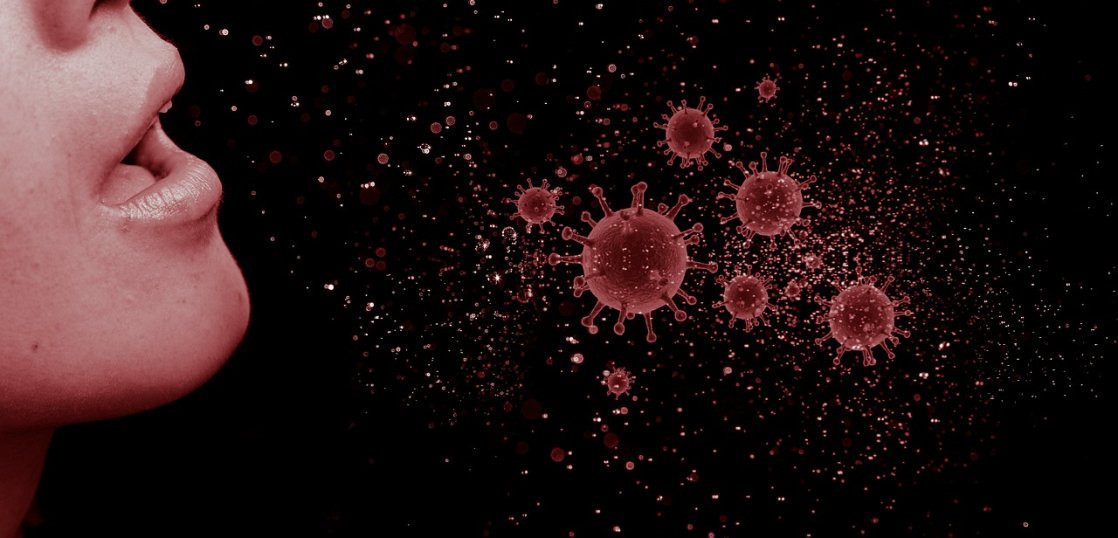

If it feels like there are multiple viruses floating around all at once, that’s because there are. With a seemingly new COVID variant every season, an unusually high number of RSV (respiratory syncytial virus) infections for this time of year, and flu season right around the corner, experts warn of a potential “tripledemic” this winter. But just how concerned should parents be?

“With regard to the ‘tripledemic,’ young children are the most vulnerable, and I’m seeing that in my practice right now,” says Dr. Mike Sevilla, a family physician based in Salem, Ore. “During the height of the pandemic, kids (and adults) have been shielded from illness with social distancing and with masking. However, as cases of flu, COVID, and RSV are on the rise nationally, we’re seeing more young children coming down with these illnesses here locally as well.”

“I think [influenza] has the potential to overwhelm our health care system,” he warns. “Unlike RSV, enterovirus—which is a group of infections that cause mild to serious illnesses—and COVID, we haven’t had an influenza season since early 2020. Influenza essentially went away for the last two and a half years, and so we have a huge population of infants—essentially almost every child in the U.S. who is under 2 and a half to 3 years old—who has not encountered influenza, and the vaccine rate is not particularly good.”

“For an individual parent, the concern for each of these viruses is not different than it’s been in the past,” Sevilla says. “But as a health care system, we do need urgent solutions to [address] a surge of influenza at the same time as RSV or enterovirus….So we need people in the community to do as much as they can to keep themselves healthy with commonsense measures and vaccines.”